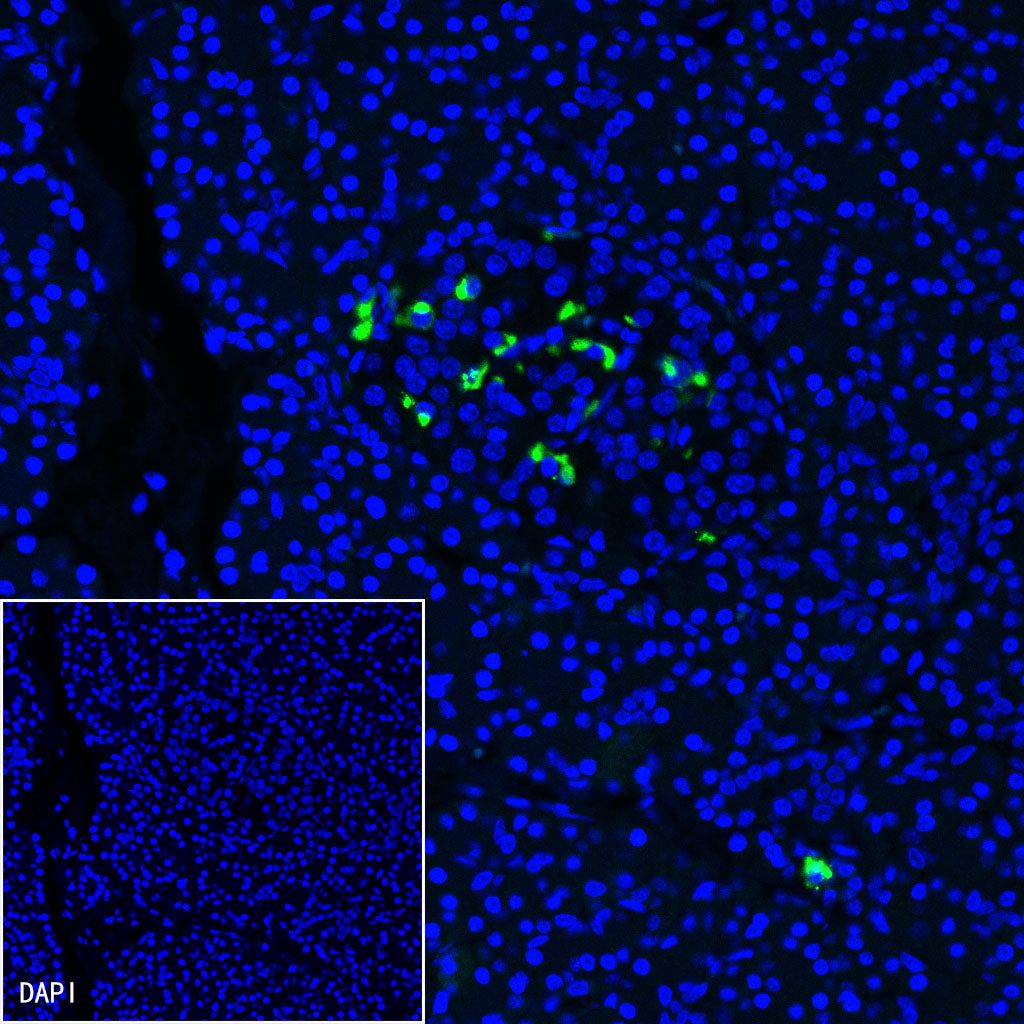

Immunofluorescence

IF shows positive staining in paraffin-embedded human pancreas. Anti-Somatostatin antibody was used at 1/250 dilution (Green) and incubated overnight at 4°C. Goat polyclonal Antibody to Rabbit IgG - H&L (Alexa Fluor® 488) was used as secondary antibody at 1/1000 dilution. Counterstained with DAPI (Blue). Heat mediated antigen retrieval with EDTA buffer pH9.0 was performed before commencing with IF staining protocol.